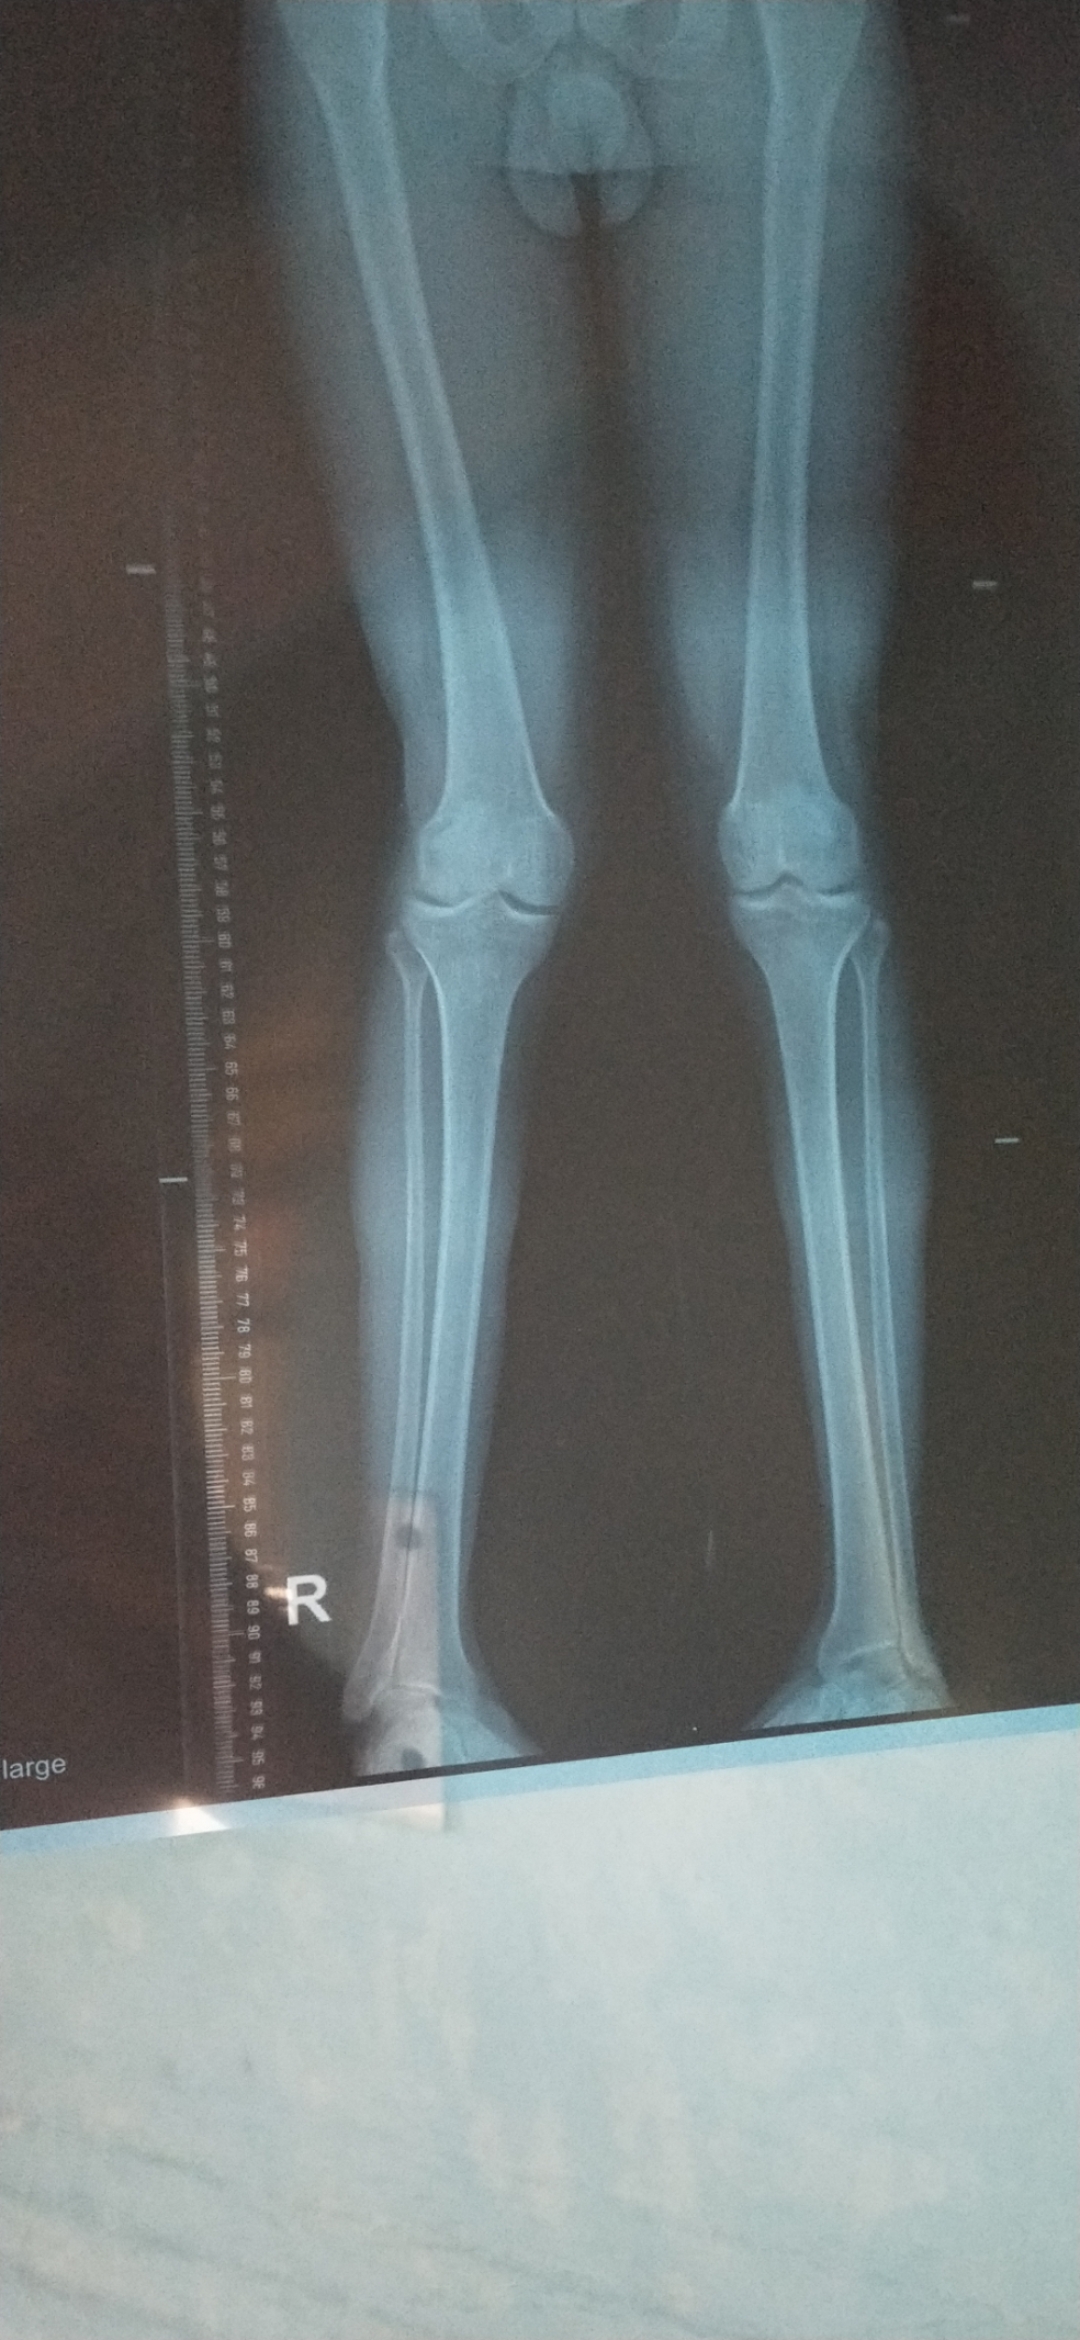

I'm student suffering from knee problem for last 1 month.

I done MRI and scannogram.

Please suggest and guide me what h can do?

Operation are mandatory or not in my case?